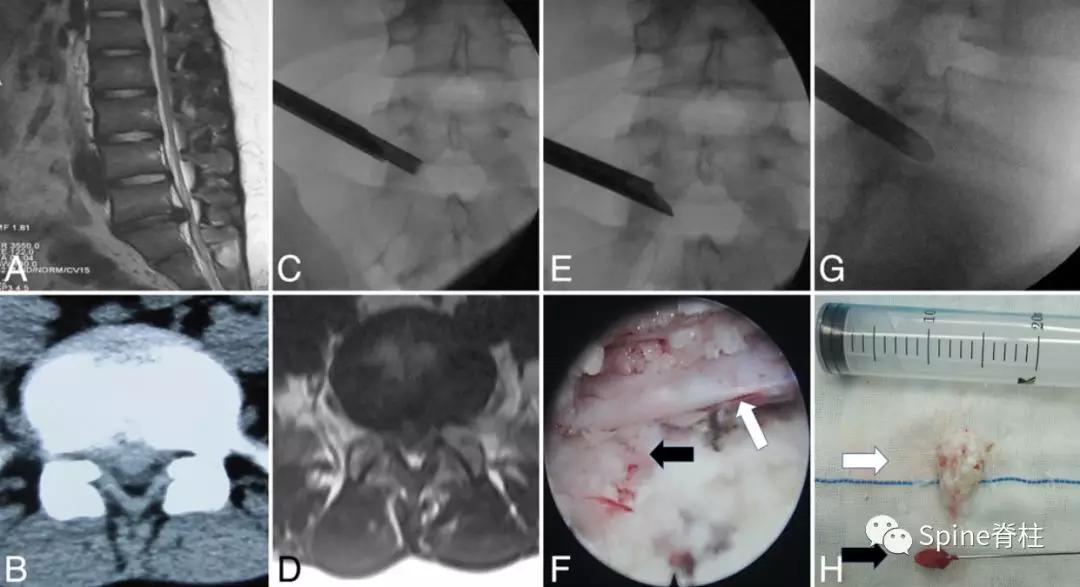

图:箭头所指为离断的椎体后缘

CT是诊断最有效的检查手段

图:A 型为分离部分含皮质骨,不伴椎体后方骨缺损(图A);B 型为分离部分较大,含皮质骨和松质骨,伴椎体后方较大骨缺损(图B);C 型为分离部分较小,含皮质骨和松质骨,伴椎体后方较小骨缺损(图C)。

由于对 腰椎椎体后缘离断症 (陈仲强)发生机理认识各异,有学者认为与青少年骺环未闭及运动创伤导致的椎体及骺环应力较大有关,也有学者认为是一种骨坏死,故命名尚未统一。